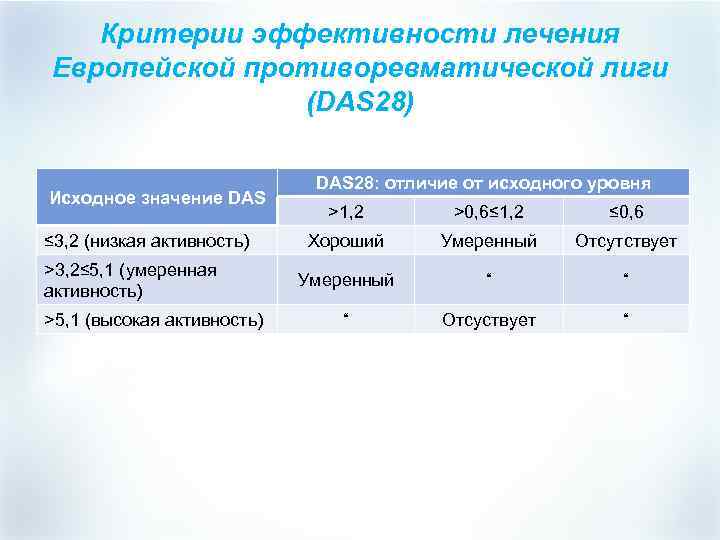

Критерии эффективности лечения Европейской противоревматической лиги (DAS 28) Исходное значение DAS ≤ 3, 2 (низкая активность) >3, 2≤ 5, 1 (умеренная активность) >5, 1 (высокая активность) DAS 28: отличие от исходного уровня >1, 2 >0, 6≤ 1, 2 ≤ 0, 6 Хороший Умеренный Отсутствует Умеренный “ “ “ Отсуствует “

Критерии эффективности лечения Европейской противоревматической лиги (DAS 28) Исходное значение DAS ≤ 3, 2 (низкая активность) >3, 2≤ 5, 1 (умеренная активность) >5, 1 (высокая активность) DAS 28: отличие от исходного уровня >1, 2 >0, 6≤ 1, 2 ≤ 0, 6 Хороший Умеренный Отсутствует Умеренный “ “ “ Отсуствует “